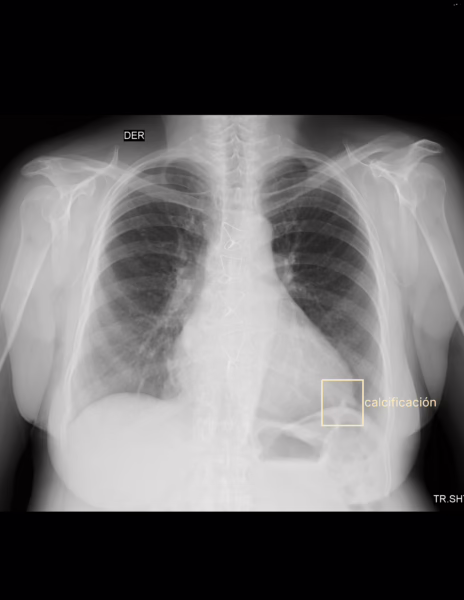

PA Y LATERAL DE TORAX

LA PROYECCION RADIOLOGICA OBTENIDA NOS MUESTRA LOS SIGUIENTES HALLAZGOS:

-Tejidos blandos, con densidad conservada, simétricos, sin evidencia de alteraciones.

-Estructuras óseas, sin evidencia de lesiones líticas, blásticas o perdida de la contigüidad. Existen escasos osteofitos marginales. Existe material metálico a nivel de esternón.

-Vía aérea permeable, con tráquea desviada hacia la derecha.

-Mediastino, central, sin evidencia de alteraciones. Botón aórtico sin calcificaciones.

-Corazón, central, con índice cardiotorácico de 0.57. Existe material radiopaco en topografía de válvula mitral.

-Hilios pulmonares, sin alteraciones.

-Trama bronco-vascular, con adecuado trayecto y calibre.

-Campos pulmonares, con adecuada densidad, sin evidencia de opacificaciones, nódulos, masas o derrame pleural

-Recesos costofrénicos y cardiofrénicos se observan libres.

-Espacio retroesternal con leve disminución de su amplitud.

OPINIÓN RADIOLÓGICA:

EN EL PRESENTE ESTUDIO RADIOGRÁFICO, SIN EVIDENCIA DE LESIONES PARENQUIMATOSAS.

CARDIOMEGALIA GRADO II.

IMAGEN DE REMPLAZÓ DE VÁLVULA MITRAL.

EXISTE ESTERNOTOMÍA MEDIA, CON MATERIAL METÁLICO.

ESTRUCTURAS ÓSEAS, CON CAMBIOS OSTEODEGENERATIVOS.

LEER DESCRIPCIÓN Y OTORGAR VALOR DIAGNÓSTICO.

CORRELACIONAR CON DATOS E HISTORIA CLINICA DEL PACIENTE

Remplazo valvular mitral